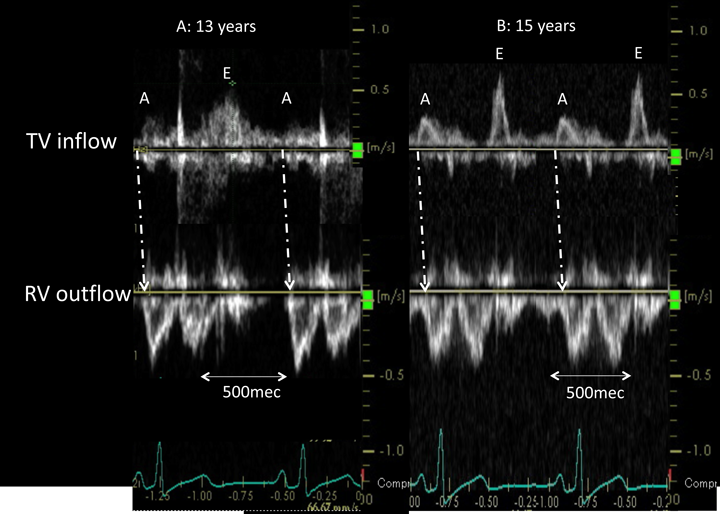

Echocardiography showed paradoxical movement of the interventricular septum in the long axis view and hypoplasia of the right ventricle in the four-chamber view. There was no shunt between the right and left atrium. Left ventricle was the compaction, and trabeculation of right ventricle was the coarse. Doppler echocardiography showed biphasic anterograde pulmonary flow (Fig. 3). One phase involved anterograde flow due to right ventricular contraction. The other involved end-diastolic forward flow to the pulmonary artery, which was consistent with the A wave of atrial contraction.

A: At 13 years. B: At 15 years. The blood flow at the RV outflow was biphasic. The anterograde flow at the end-diastolic phase corresponded with an atrial contraction. However, the magnitude of A wave is smaller at age 15 than at age 13 years. RV, right ventricle; TV, tricuspid valve.

In the waveform of the right ventricular inflow portion, the interval between the E wave and the A wave was flat, and the diastolic disorder of the right ventricle was suspected. Fig. 4 shows the pressure wave form of the cardiac catheterization. The increases in the pulmonary arterial pressure and right ventricular pressure were consistent with an increase in atrial pressure with the atrial A wave. The pulmonary artery pressure increased as the right ventricular pressure increased at 13 years of age. However, when cardiac catheterization was performed at 15 years of age, the increase in the right ventricular end-diastolic pressure. Moreover, the waveform of this right ventricle clearly showed a dip and plateau. We thought that the restrictive myocardial myopathy had worsened.

Due to the progression of the right ventricular restrictive change, a high atrial contraction pressure was required for auricular contraction to generate pulmonary blood flow. In fact, the magnitude of the A wave at age 15 was smaller than at age 13 (Fig. 3).